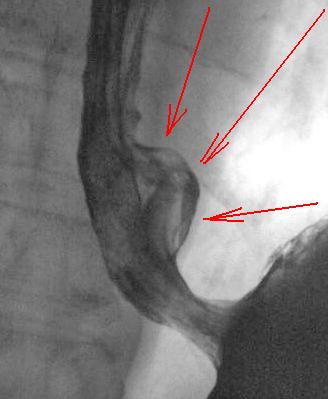

Осмелюсь предположить что в антральном отделе желудка есть рак,  инфильтративная форма.

На серии представленных вами снимков сделанных во время скопии, отмечается регидность участка и утолщение слизистой(отмечено стрелками), жалко только  что не была выведена петля 12п.к. в положении стоя, там бы мы увидели четко антральный отдел:

В антарльном отделе  не толко ригидность ,а стойкое циркулярное сужение.А вот по большой кривизне можно сказать ,что ригидность, хотя контур стенки ровный четкий, но при двойном контрастировании толком не расправился, да и перистальтика почти отсутствует

Протяженность процесса, учитывая зазубренность большой кривизны, надо думать была значительная?

Надо думать, что в антральном отделе, по большой кривизне, имела место быть "чашеподобная" карцинома, со значительным изъязвлением?

Насколько "процесс" распространился на поджелудочную железу?

операции пока не было, однако по данным УЗИ процесс распростраяется на поджелудочную железу по типу инфильтрации.